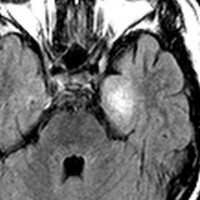

10才の時に,複雑部分発作(症候性てんかん)で発症しました。吐き気を感じた後に嘔吐して意識が遠くなる(意識減損)という症状であり,側頭葉てんかんです。脳波では左側頭葉に徐波律動がみられました。発作は頻回でしたがカルバマゼピンの投与で抑制されていましたが,MRIで腫瘍が発見されました。

左内側側頭葉グリオーマ mesial temporal glioma と呼ばれる腫瘍です。左の扁桃体,海馬鉤,海馬,海馬傍回に腫瘍が浸潤しています。T2強調画像とFLAIRでまだらな高信号で境界ははっきりしません。mass effectが少なく,増殖増大傾向のある腫瘍には見えないのが特徴です。下段右のように部分的にガドリニウム増強されるのも神経節細胞腫の特徴かもしれません。しかし,神経節膠腫,乏突起膠腫,乏突起星細胞腫(グレード2)なども疑われます。

手術中の脳波モニターでは,棘波が上側頭回の後方(ウェルニッケ領域)に存在し,深部電極刺入で海馬近傍にも棘波がみられましたが,もちろん上側頭回や海馬の切除はしませんでした。扁桃体 amygdala と海馬鈎 uncus の腫瘍部分のみを切除して手術を終了しています。海馬と海馬傍回には腫瘍を残しました。上のMRIは,その後6年経過した後のものですが腫瘍は全く同じ大きさです。抗てんかん薬も止めて,発作は全く生じていません。このような腫瘍は,扁桃体と海馬鉤を摘出することで,発作を完全に止めることができることがあります。ですから,最初の手術では,リスクのある余分な脳切除をしません。